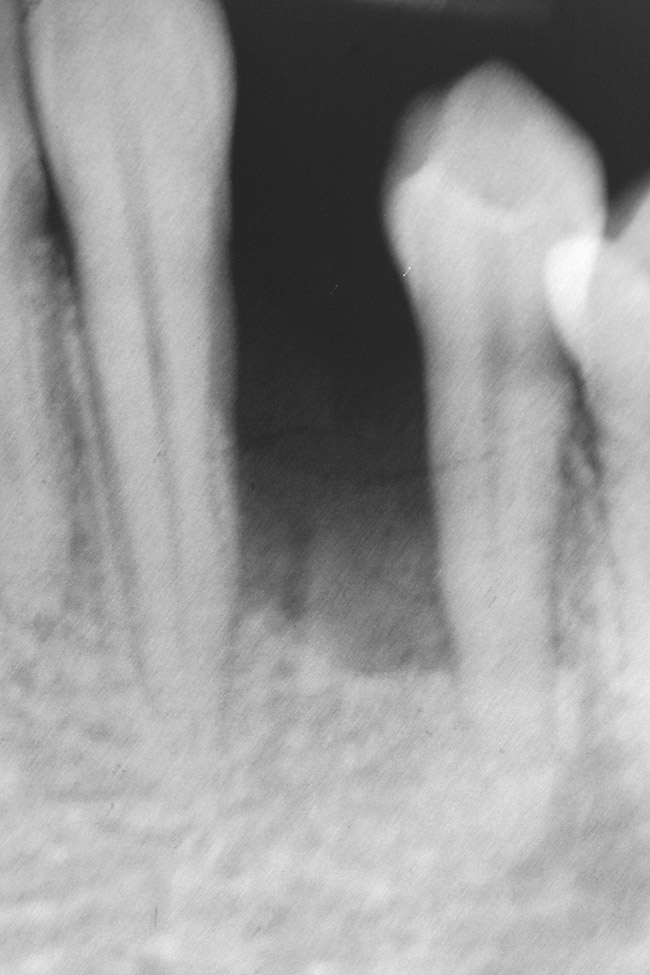

Figure 7  Radiograph of residual ridge defect in site No. 22.

Figure 7

The patient had no medical concerns and had a history of an implant placement in December 2002 when she was 25 years old. In February 2005, she presented with a mobile implant and an associated advanced peri-implantitis. Radiographic review at the initial examination demonstrated significant destruction of the dentoalveolar ridge around the implant as well as around the adjacent natural dentition. Emergency-based treatment involved surgical implant removal only and debridement of the infection (Figure 4 and Figure 5). Following uneventful healing, an advanced ridge defect was apparent at the edentulous site and moderate and advanced attachment loss noted at No. 22D and No. 21M, respectively (Figure 6 and Figure 7). This case demonstrates bone loss of two separate origins: lack of bone because of tooth agenesis and destruction of bone from inflammatory peri-implantitis.